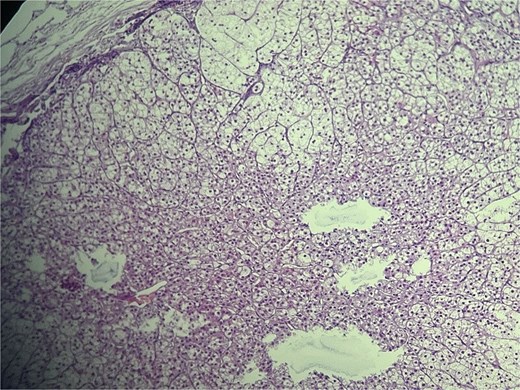

Microscopic evaluation (hematoxylin and eosin) demonstrated an endometrial polyp without atypia, multiple leiomyomas, and bilateral benign serous cystadenomas. Sections from the left fallopian tube and adjacent mesosalpinx revealed a small, well-circumscribed nodule (~3 mm) within the mesosalpinx (Figs 1–3). The nodule was composed of bland polygonal cells with distinct borders and clear to finely granular eosinophilic cytoplasm. Nuclei were round to oval, centrally located, and uniform, without pleomorphism, hyperchromasia, necrosis, or increased mitotic activity. The cells were arranged in nested/trabecular architecture resembling zona fasciculata; no medullary component was identified. These features supported the diagnosis of ectopic adrenal cortical tissue.

High-power view of ectopic adrenal cortex composed of polygonal cells with finely vacuolated, lipid-rich cytoplasm, and round to oval nuclei, arranged in nested/trabecular patterns resembling zona fasciculata. No medullary tissue is present. H&E stain, ×100.